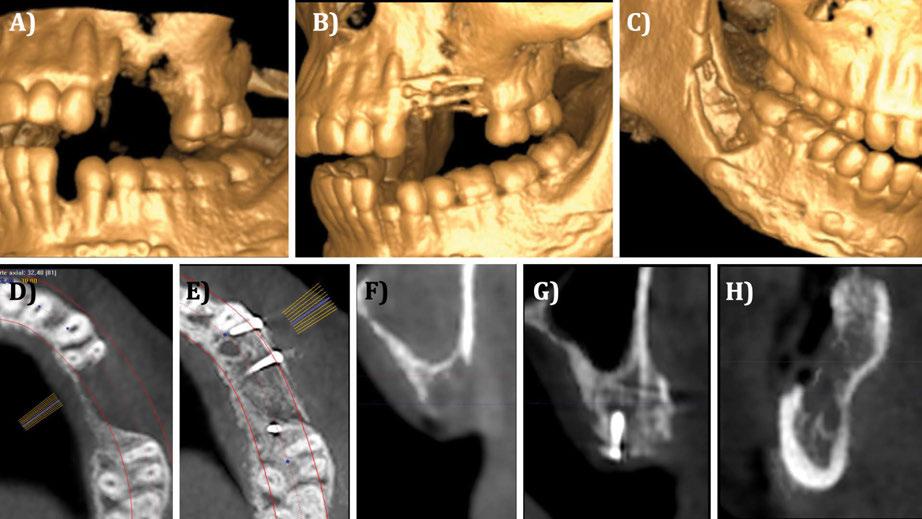

Figura 1. Caso clínico con membrana no reabsorbible (Goretex®). A) Situación radiográfica (2D) basal. B) Situación radiográfica (3D) basal.

Figura 2. Caso clínico con membrana no reabsorbible (Goretex®).

Figura 3. Caso clínico con membrana no reabsorbible (Goretex®). Continuación. A) Fresado para la colocación del implante. B) Colocación del implante en la posición tridimensional adecuada. C) Relleno del defecto óseo con `chips´ de hueso autólogo del propio paciente.

Figura 5. Caso clínico con membrana no reabsorbible (Goretex®). Continuación. A) Sutura y cierre primario. B) Situación radiográfica 2D inmediata post-operatoria.

Figura 6. Caso clínico con membrana no reabsorbible (Goretex®). Continuación. A) Reentrada. Vista vestibular. B) Reentrada. Retirada de la membrana. Vista vestibular. C) Reentrada. Retirada de la membrana. Vista oclusal. D) Aspecto oclusal-crestal del implante. reabsorbibles frente a un 90,9% de los implantes colocados tras injertos de bloque autólogos, a 2 años de seguimiento tras la carga protésica. En relación al tipo de politetrafluoretileno (PTFE) que se puede utilizar en estas membranas no reabsorbibles, es necesario distinguir que el clínico tiene a su disposición membranas de PTFE denso (d-PTFE) o expandido (e-PTFE), siendo las segundas las que más respaldo científico tienen en la actualidad (Urban y cols 2019).

Figura 4. Fijación de la membrana no reabsorbible (Goretex®).

Ciencia. CIENCIA

7. Caso clínico con membrana no reabsorbible (Goretex®). Continuación. A) Injerto de tejido conectivo autólogo. B) Sutura y cierre primario. C) Situación radiográfica tras carga protésica. D) Situación clínica tras carga protésica.

8. Caso clínico con membrana no reabsorbible (Goretex®). Comparación en vista oclusal. A) Defecto óseo inicial. B) Situación ósea en reentrada. C) Contorno vestibular tras carga protésica.